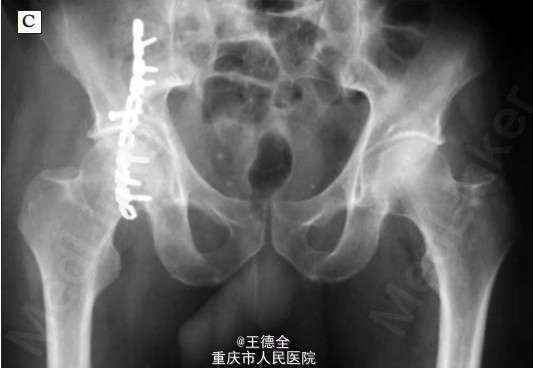

右侧髋部骨折一例

患者男性,42岁,车祸伤入院,完善检查后发现右侧髋部骨折,遂手术治疗。